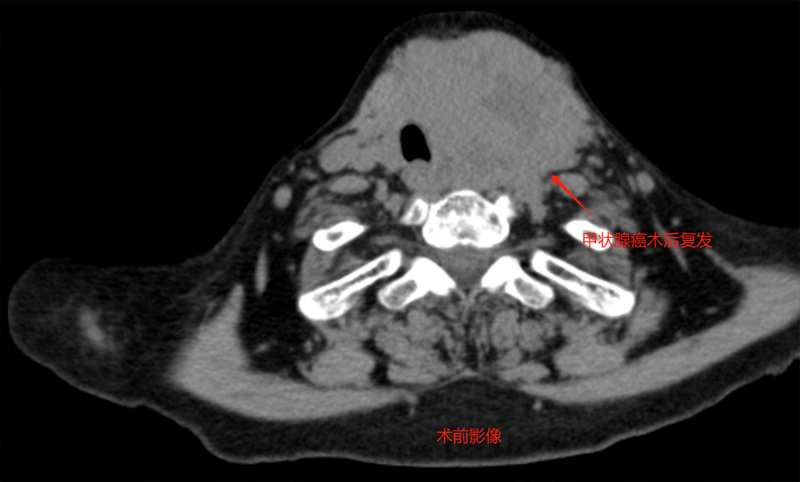

家住内蒙古的苑大娘两年前就被确诊为甲状腺恶性肿瘤,2022年9月她在吉林省某三甲医院行“双侧甲状腺全部切除术”,术后病理示为:【双侧甲状腺】(左侧)甲状腺滤泡癌 广泛浸润型。本以为做完手术就高枕无忧的她一周前突然出现呼吸困难,活动后加重,左侧颈部可触及肿大结节,于是在家人的陪同下再次来到医院检查,甲状腺超声提示:结节大小约7cm,气管双侧低回声,双侧颈部可见小淋巴结,考虑甲状腺癌复发可能性大。

得知自己术后仅两年便再次复发,苑大娘便觉晴天霹雳,本想再次行手术治疗,却因已进行过手术切除同时复发瘤体与气管关系紧密,并包绕多根重要血管而被告知不能手术,苑大娘一家陷入了困境。